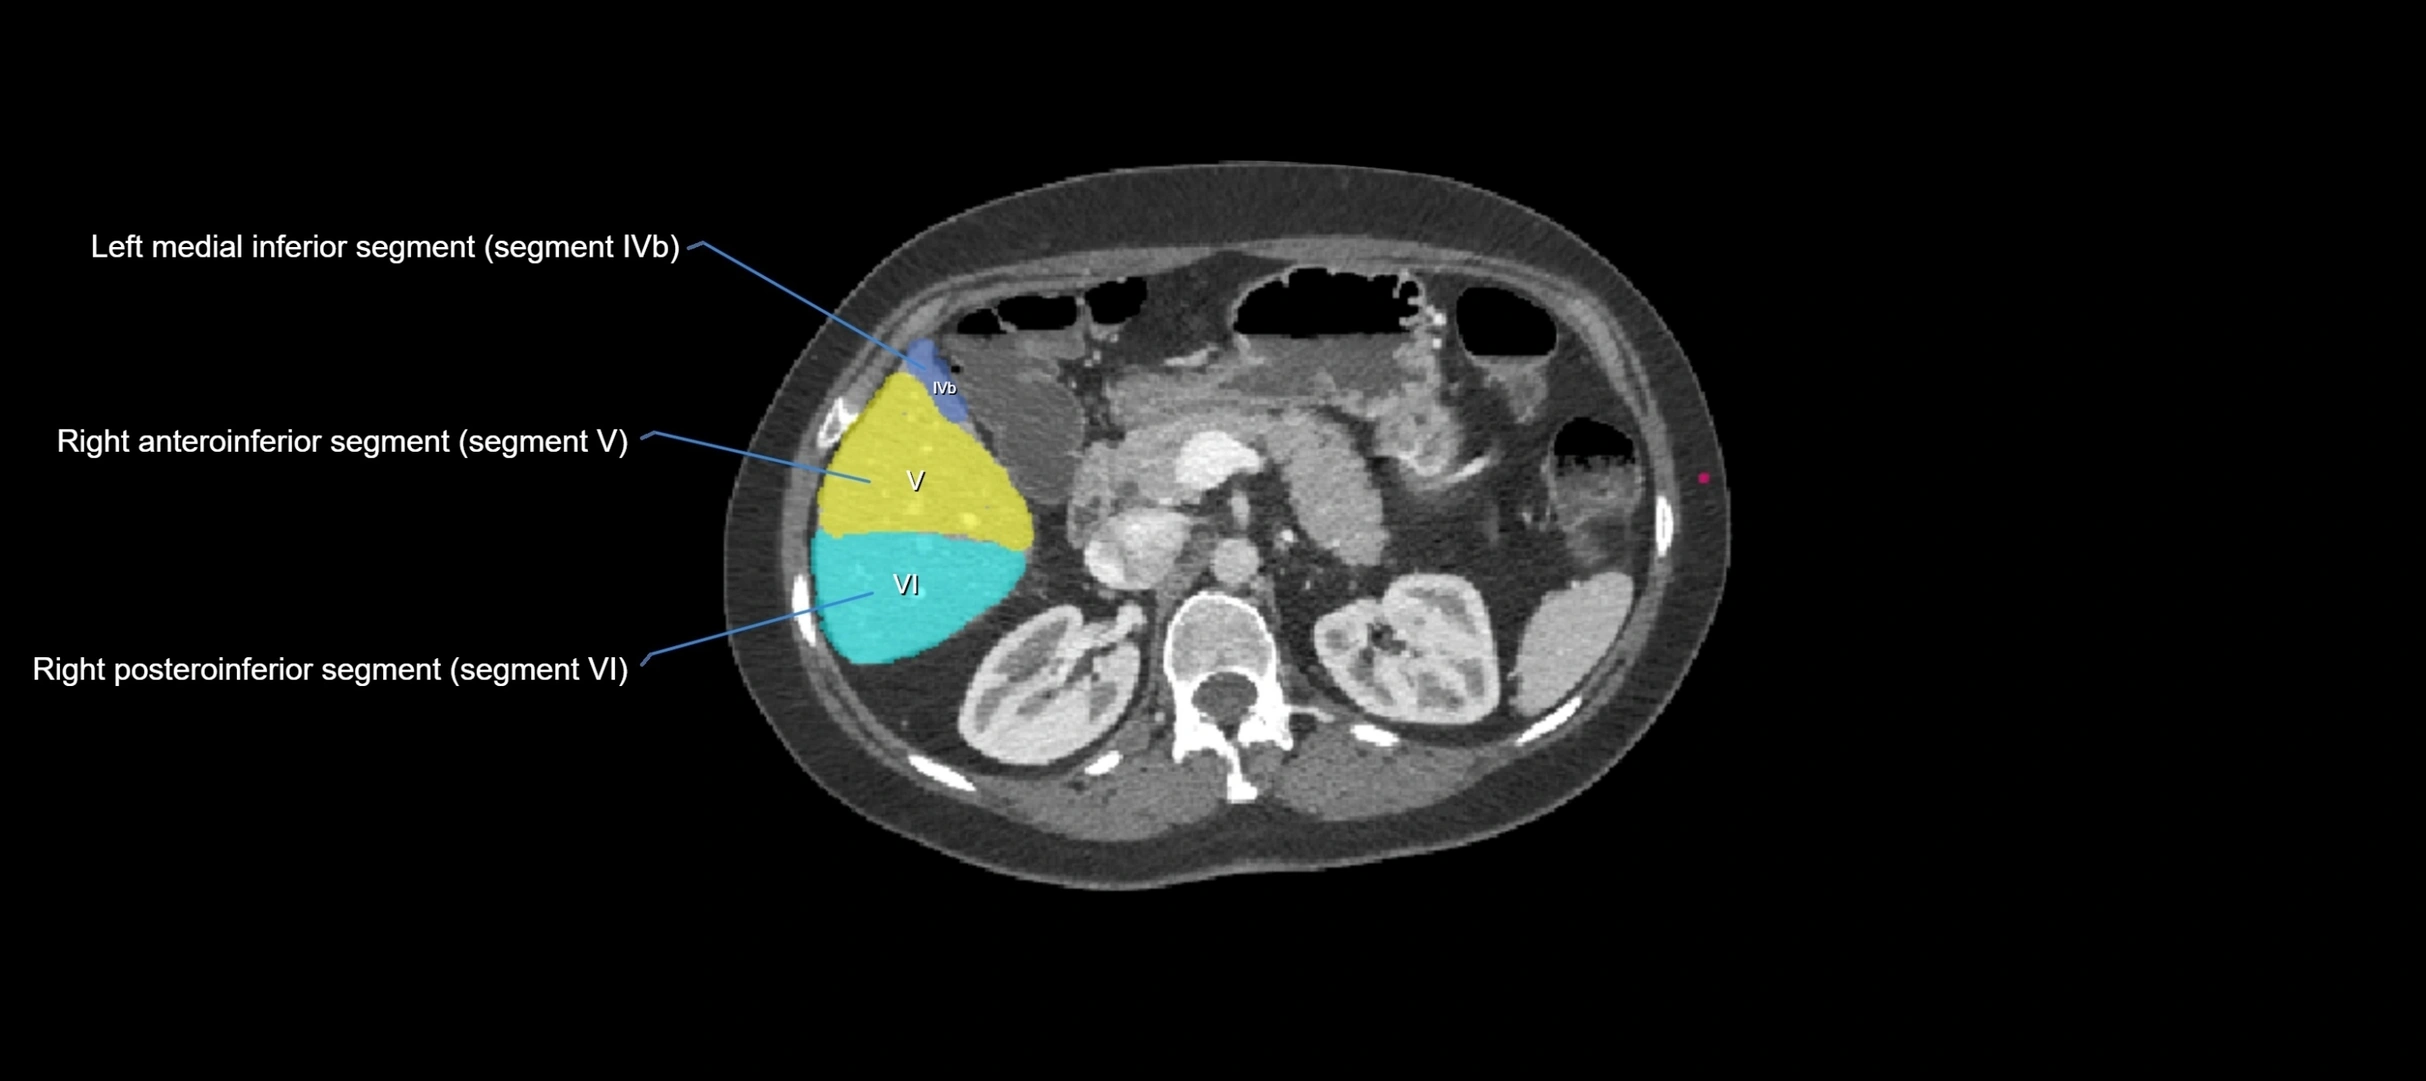

CT Image

image